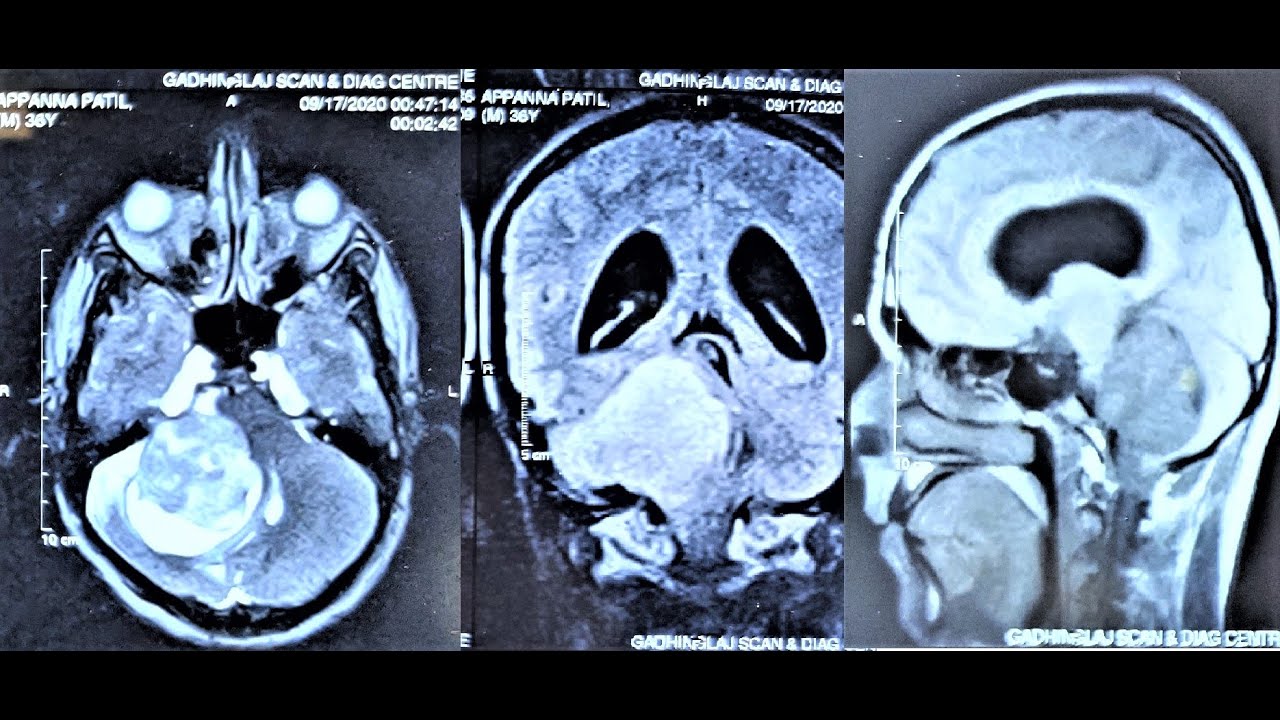

Facial nerve tumor

Facial nerve tumor 114 photos